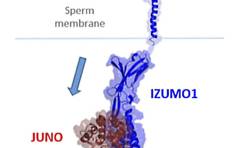

Perikonzeptionelles Rauchen beeinträchtigt Embryonal- und Fetalent-wicklung / Protein im Oolemma wichtig für Spermienbindung / Rektusdi-astase / Keine Wartezeit nach Abort / Amlodipin oder Nifedipin bei Schwangerschaftshypertonie? / Weniger als sechs ... PDF Dokument